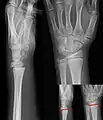

Изображения эпифизеолиза

- Рентгеновские снимки переломов Салтера-Харриса с вставками где показаны линии перелома

I тип — перелом дистального метаэпифиза лучевой кости.